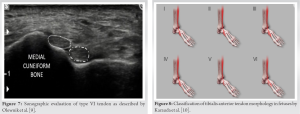

Clubfoot was described in Egyptian hieroglyphs and was described by Hippocrates [1] around 400 BC. He advised treatment with bandages and manipulation “manipulate the foot as if holding a wax model, not by force, but gently.” In 1929, Böhm [2] wrote at the beginning of his article on CTEV: “I feel there is a deficiency in the field of scientific orthopedic surgery relative to the question of the origin of the deformities and their pathological anatomy.” Although the topic CTEV has been extensively researched but still lacks a consensus concerning the etiology, pathogenesis, treatment, and its associated syndromic and non-syndromic associations. Idiopathic CTEV is associated with joint laxity, congenital dislocation of the hip, tibial torsion, ray anomalies of the foot, absences of some tarsal bones, and history of other foot anomalies in the family [3,4]. In CTEV, the ligaments on the medial and posterior sides of the tarsal and ankle joints are extremely thick and stiff, causing the foot to remain in an equinus position with the calcaneus in inversion and the navicular in adduction [5]. The severity of a CTEV malformation is inversely proportional to leg muscle size. In the most severe cases, the gastrosoleus muscle appears as a minute muscle in the proximal portion of the calf. Excess collagen formation in the muscles, tendons, and ligaments can result in relapses up until the age of 3–4 years [6]. Residual dynamic and structural deformities following clubfoot surgery are commonly due to residual muscle imbalance from a strong tibialis anterior muscle (TAM) and weak antagonists. When the child walks, the strong tibialis anterior produces dynamic supination. It can also be a contributing factor in cavus deformities, hindfoot varus and forefoot adduction, and other structural deformities, such as rotatory dorsal subluxation of the navicular following surgical treatment [7]. TAT transfers from base of the first metatarsal to cuboid changes the vector of pull of the muscle and helps to correct the dynamic supination. In this particular case report, we would like to discuss one such muscular anomaly, i.e., bifid TAT. TAM belongs to the anterior compartment of the leg, it arises from the lateral condyle of tibia, and upper two-thirds of lateral surface of tibia. Its distal attachment is on the medial cuneiform and base of the first metatarsal. It plays a role in dorsiflexion and inversion of the foot and is supplied by the deep peroneal nerve [8]. The insertion of TAM is morphologically variable, which has led many authors to develop various classification systems. The most common variant is the occurrence of an additional band but may also have an third band [9]. In a comprehensive review by Zielinska et al., anatomical variants of the TAT insertion describes the classification system of morphological variants of TAM insertion by Olewnik et al. in adults and Karauda et al. in fetuses [10]. Interestingly, Olewnik et al. divided their research into two parts: an anatomical part, which included the anatomical preparation of the TAT in cadavers, and a sonographic part, which included the USG examination in human subjects (Fig. 6). Type I is characterized by two insertions of equal size located on the medial cuneiform and the first metatarsal. Type II is represented by two bands, the wider one inserted on the medial cuneiform and the narrower one on the base of the first metatarsal; this was the most common type in the subjects in the sonographic study. Type III was characterized by the tendinous portion splitting into two ligaments, one inserted at the medial cuneiform (smaller portion) and the other at the base of the first metatarsal (larger portion). As mentioned above, type IV was only observed in the anatomical part of this study; no sonographically examined specimen showed this type. It was characterized by three tendons, one of which attached distally to the medial cuneiform bone, the other two to the base and shaft of the first metatarsal. Type V was characterized by a single ligament attached to the medial cuneiform bone, and this was the most common type among the dissected cadavers. The presence of Type VI was only detected on ultrasound examination; it consisted of two equal-sized ligaments, both attached to the medial cuneiform bone [9] (Fig. 7). The classification system for fetuses proposed by Karauda et al. was based only on the anatomical part of the study of adults (characterized by five types) (Fig. 8). A new type of TAT was identified in fetuses; it has been called type VI. Importantly, it is not the same as type VI (two equal-sized ligaments attaching to the medial cuneiform bone) identified in the sonographic part of the study by Olewnik et al. In the fetuses, type VI was characterized by the tendinous part of the TAM being divided into three distinct ligaments. The distal attachment of the smallest component was at the medial cuneiform bone. The middle and larger components attached to the base of the first metatarsal. This type was found in four lower limbs (two right and two left). It was the basis for the extension of the previous classification. Although the fourth type (three distal attachments, one to the medial cuneiform, and two to the first metatarsal [base and shaft]) was not found in this group, it was not removed from the classification. One possible reason for its absence could be that the group of fetuses was too small; type IV could possibly be found in a larger population of fetuses. However, considering that the characteristic feature of type IV is its three distal appendages, it is possible that the thinnest tendon has not yet developed in fetuses. Other morphological variations of the TAT in fetuses were similar to those in human adults. For example, type I was characterized by a tendon component divided into two ligaments attached to the medial cuneiform bone and the base of the first metatarsal; and type II had the larger component attached to the medial cuneiform bone and the smaller component attached to the base of the first metatarsal. A similar morphological variation is also associated with type III, which is characterized by a tendon component divided into two distal attachments located at the medial cuneiform bone (smaller component) and at the base of the metatarsal bone (larger component). The final example of a close resemblance between fetuses and adults is type V, which had a single ligament attached to the medial cuneiform bone [7]. In our case, we found the tendon split into two equal parts being attached to the medial cuneiform and base of 1st metatarsal which is equivalent to type I, according to the classification proposed by Olewnik et al. Hence, it is important to consider the possibility of a bifid TAT when undergoing a tendon transfer for dynamic supination. It might be feasible to perform an ultrasonographic evaluation preoperatively to have a better understanding before performing the procedure to avoid under correction of the deformity.